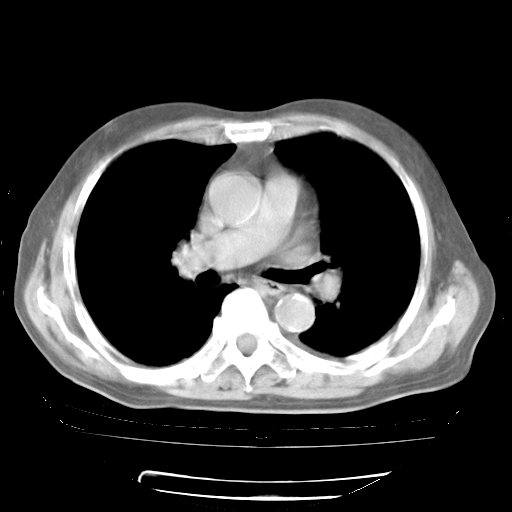

4月28日肺部CT——再次出现类似去年5月9日——透光度降低,“间质性”改变。

4月28日肺部CT

个人阅读4.14日肺部CT平扫:纵隔窗无异常,但肺窗示:双下肺内、后基底段有片絮状侵润影,部位以后基底段为著,以间质改变为主,呈急性肺泡炎征像,和首次住院影像学有相似之处。仅是个人读片,明日请相关专家再读片哈。其它建议同上。

1、108#的是4月14日的胸部CT(发此贴时还没看着28日的CT)。14日的胸部CT其实已经出现改变(如108#所述),个人认为28日的胸部CT除纵膈窗疑似有双侧胸膜增厚或少量胸积液(可行胸部B超明确)外,与4月14日对照病变有所加重;2、已经给予“异烟肼、利福平、乙胺丁醇”抗痨治疗?如果是,甲强龙80mg可缓慢减量;如果环磷酰胺已停用,暂不使用;3、中性粒细胞92%,明显升高,目前体温情况?注意合并细菌感染可能,使用左氧氟沙星情况下,是否联用B-内酰胺类抗菌药物?另外是查免疫全套非风湿全套。

今请临免主任会诊后认为:4月14日胸部CT已有双下肺间质性改变。患者病情复发多系激素减量过快不正规所致。目前甲强龙80mg/日,一周后酌情开始减量,不易过快。环磷酰胺若已停用,暂不使用。他同意目前抗菌药物使用,但应考虑是否加用B-内酰胺类抗菌药物(中性细胞明显增高);2、结核复发目前依据不足;3、若免疫全套各项指标正常,考虑多系特发性肺间质炎可能大。4、加强支持,并注意保护胃黏膜。

今上午去请教了临免、呼吸主任:1、介绍病史和阅读系列胸部CT一致认为:患者肺结核不考虑,仍为肺间质纤维化,目前处于急性肺泡炎阶段。2、若仍发热,可将甲强龙增至:80mg Bid静滴,同时鉴于中性增高,合并细菌感染可能,继续左氧氟沙星治疗,再联用B-内酰胺抗菌药物,如头孢哌酮--舒巴坦;3、停用抗痨药;4、目前甲强龙每日剂量160mg ,体温正常后再酌情减量;目前暂不用免疫抑制剂;4、不建议使用免疫增强剂等;5、加强支持治疗,鼓励患者进食;5、注意随访肝、肾功及血常规情况;6、因患者目前激素用量较大,加用胃黏膜保护剂,防止消化道出血可能。